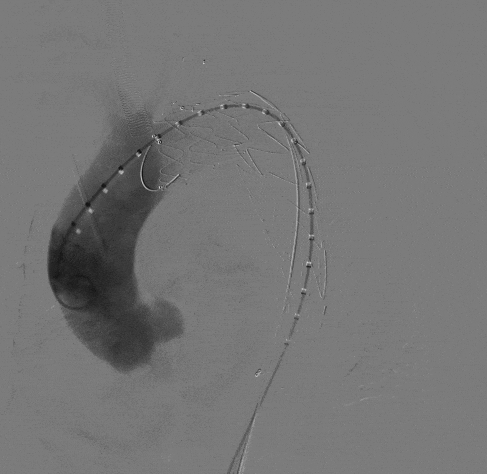

2、随后撤出长鞘,从右侧股动脉沿超硬导丝上推输送系统至降主动脉,在褪下输送系统外管后,上推支架,在定位精准后,撤掉部分支架软鞘露出分支支架,助手配合牵拉分支导丝,使分支支架进入LSA。

动脉长鞘怎么置入宁波市第二医院血管外科运用Castor®单分支支架结合长鞘建立导丝通路的方法治疗Stanford B型胸主动脉夹层一例_https://www.jmylbn.com_新闻资讯_第8张

褪下部分软鞘后,牵拉分支支架进入LSA

动脉长鞘怎么置入宁波市第二医院血管外科运用Castor®单分支支架结合长鞘建立导丝通路的方法治疗Stanford B型胸主动脉夹层一例_https://www.jmylbn.com_新闻资讯_第9张

褪下剩余软鞘

3、再次造影确认支架位置准确后,快速释放主体支架,助手配合牵拉分支导丝释放分支支架。